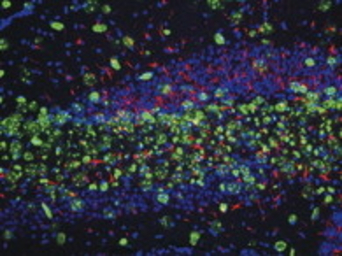

IHC analysis of mouse brain tissue sections (hippocampus, CA3 region) from 21 day old mice 72 hrs after dosing with trimethyltin using GTX26142 Nestin antibody [2Q178].

Blue : Nissl (rough ER)

Red : nestin (Primary antibody)

Green : lectin IB4 (microglia) or GFAP (glial fibrillary acidic protein, astrocytes)